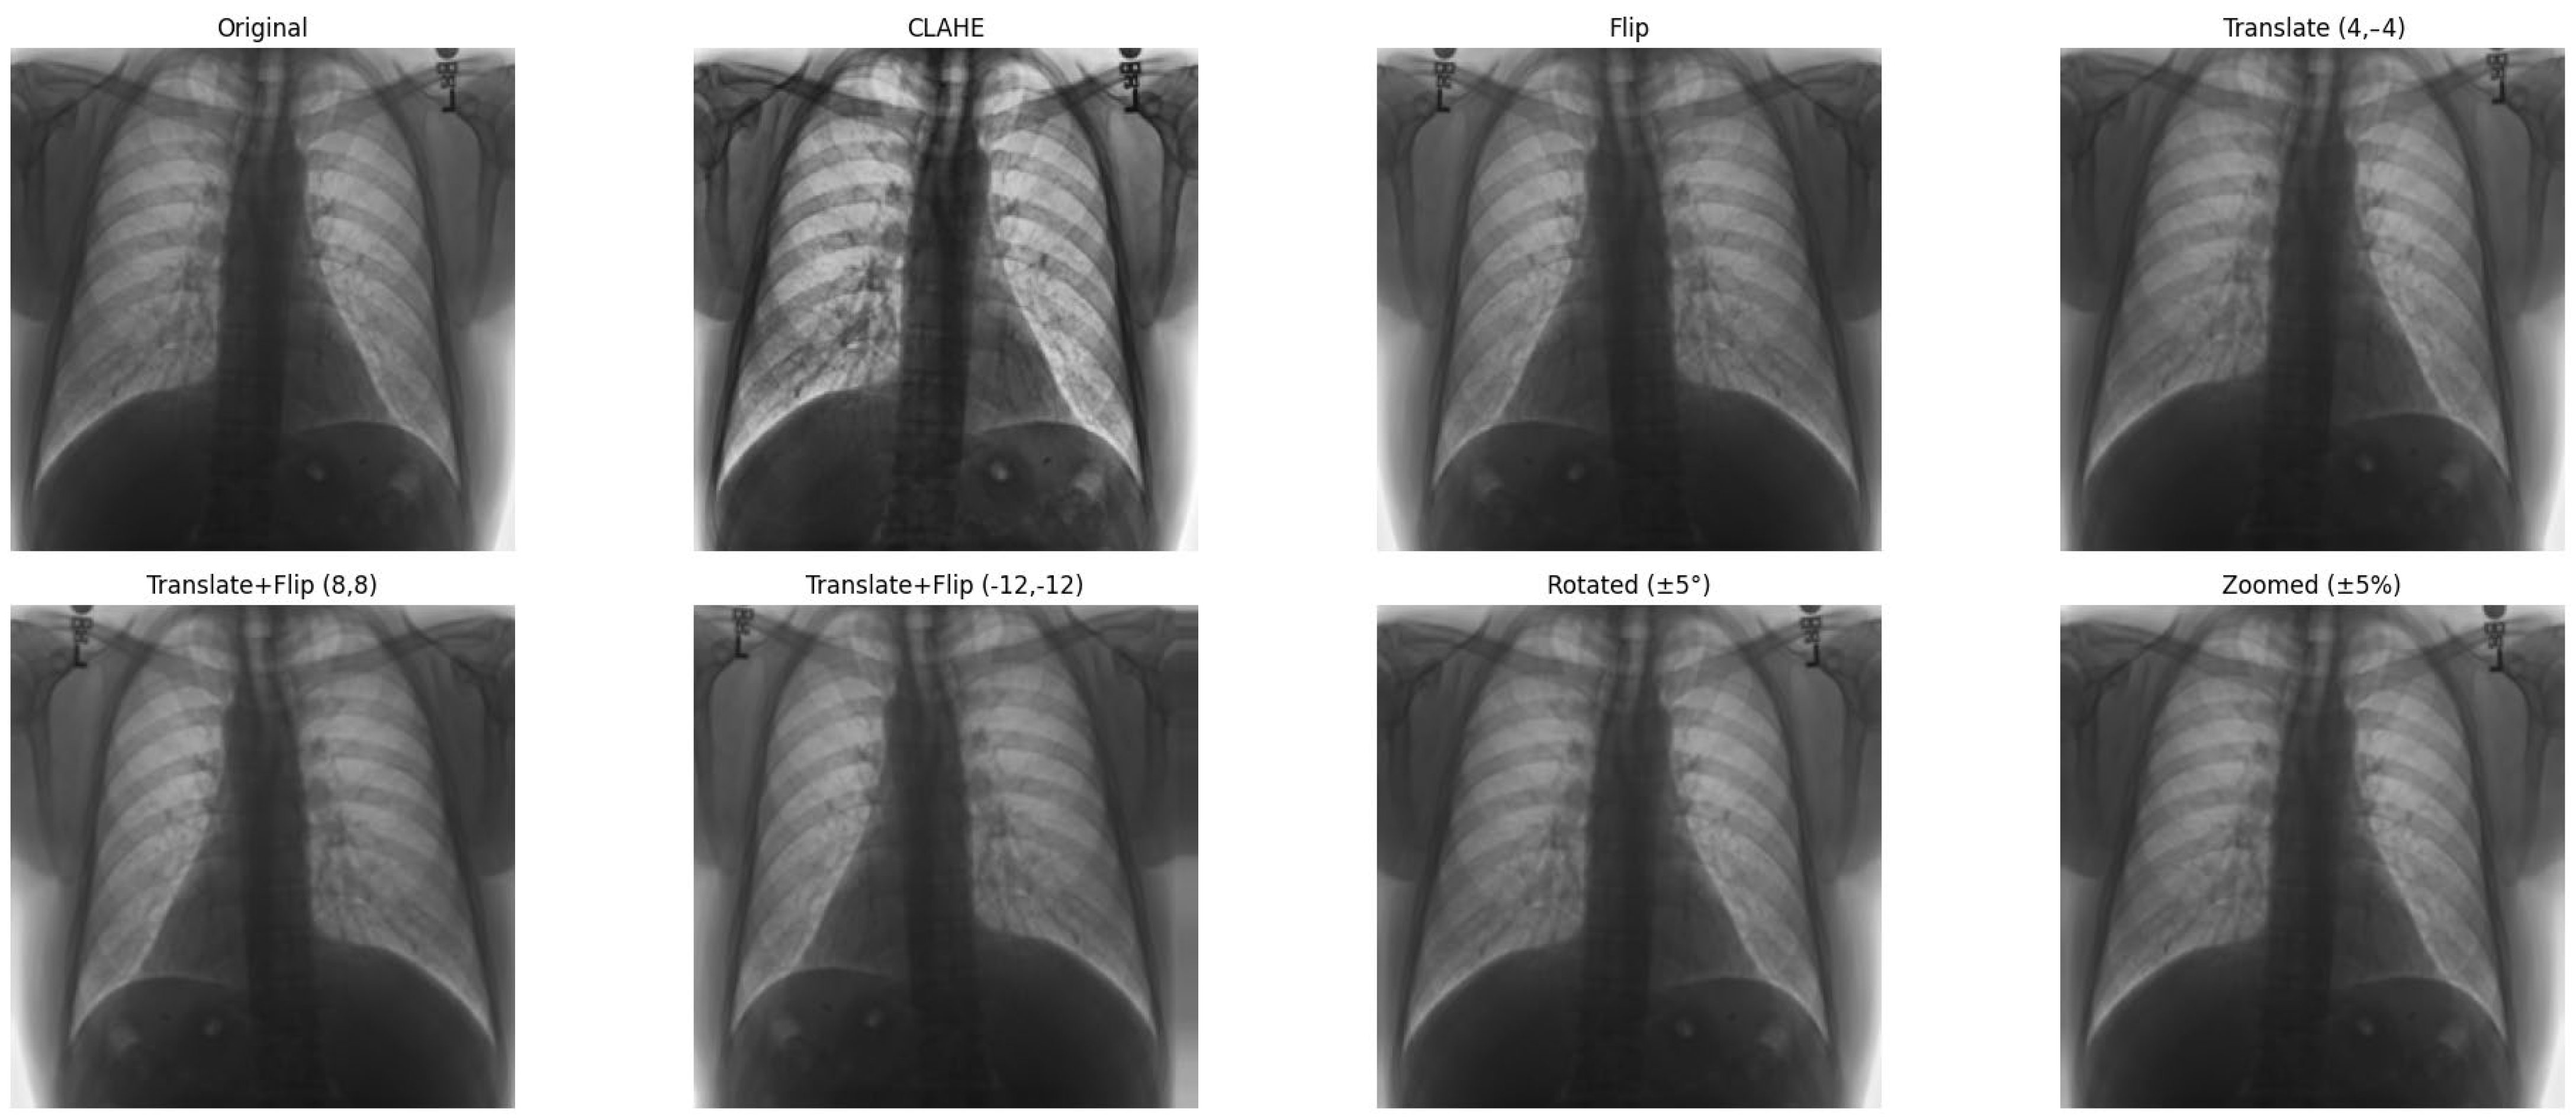

- CXR: The visualization of the heart’s size and shape, often used as a preliminary diagnostic tool. Moreover, the Cardiothoracic Ratio (CTR) is a diagnostic metric utilized to identify cardiomegaly (an enlarged heart) in CXRs captured in the posteroanterior (PA) view. In order to determine this ratio, the maximum horizontal diameter of the heart is divided by the maximum horizontal diameter of the thoracic cavity, which is measured at the inner edges of the ribs. An average CTR ranges from 0.42 to 0.50. A CTR exceeding 0.50 is indicative of cardiomegaly, thus signaling the presence of an enlarged heart. For a visual representation, refer to Figure 2, which demonstrates a sample CXR used for CTR calculation.

Figure 2.

The approach to calculating the CTR involves measuring the relationship between the transverse diameter of the heart (denoted as [A]) and the transverse diameter of the chest cavity (denoted as [B]), as observed on a chest radiograph taken in the posteroanterior (PA) view. The CTR is then computed using the following formula: CTR = A/B [7].